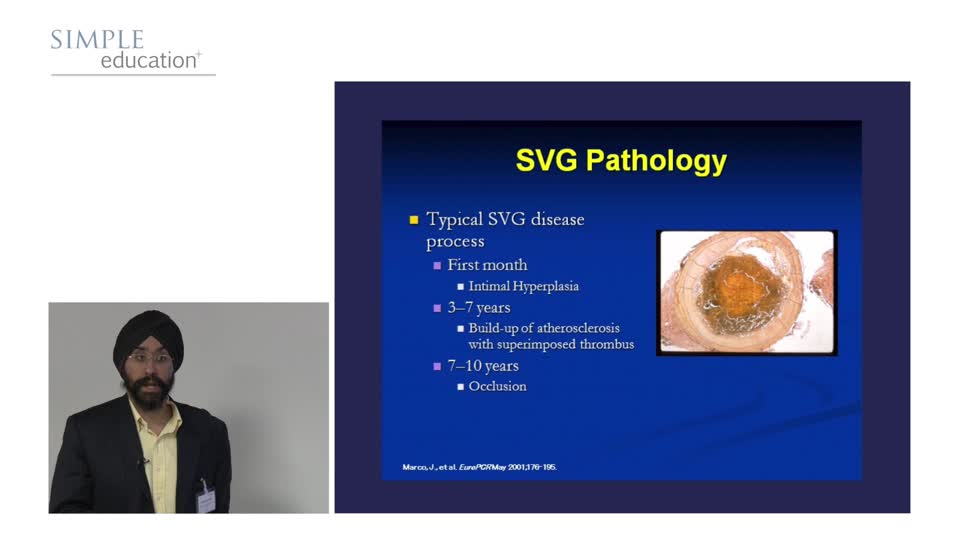

Graft Cases - Don't Panic! We'll Show You How to Make Them Easy! - Amarjit Sethi

Simple Education